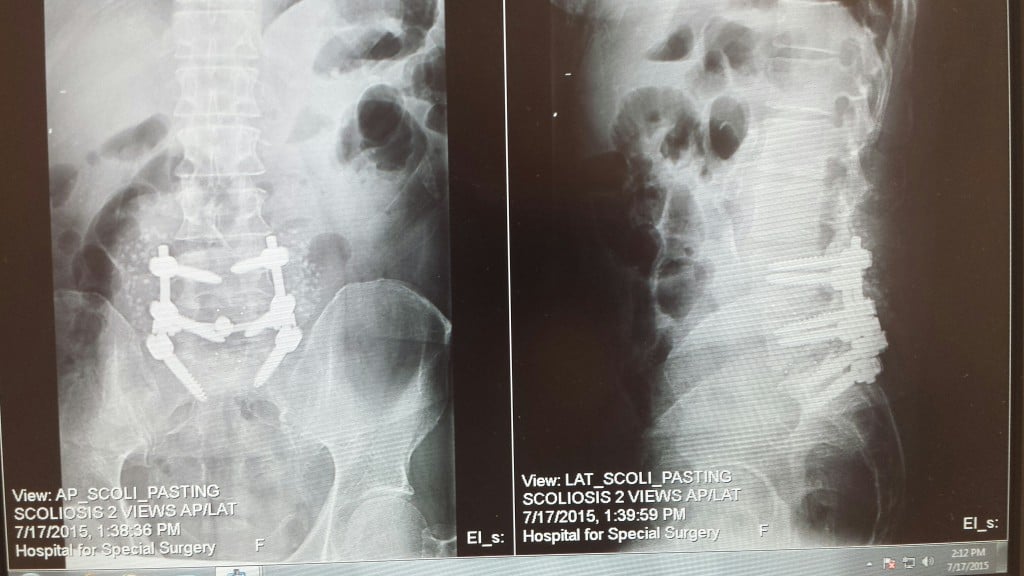

As a 23 year old guy, I never anticipated to suffer from severe back pain. I'm young, active and have a demanding job as a sports producer which sometimes involves carrying a camera for shoots. So in November of 2014, after a pick-up football game with friends, I tried to ignore the slight discomfort I felt but by March of 2015 the pain was unbearable. I shuffled my feet to walk and never slept. With the encouragement of my family, I got an appointment with Dr. James Kinderknecht. Dr. K was knowledgeable, friendly and attentive. I left that appointment with a clear plan and diagnosis - I was suffering from sciatica, a result of a herniated disc that was trapping my sciatic nerve. Dr. K recommended I meet with his colleague Dr. Andrew Sama. Dr. Sama was great! He explained that a microdiscectomy was the best route - removing the piece of the disc that was pressing on my nerve. I had surgery at HSS in April. The best part - in the recovery area post op...I was already pain free despite spine surgery! Much to my family's surprise - I was cleared to go home same day. Recovery was a process but I was up and walking the next morning. One month later I was at a friend's wedding. Two months after that - I was on vacation in Portland, OR. I was back at work in 4 weeks. As much as no one wants to hear they want surgery - it was the best decision I ever made. HSS is a great hospital and I'm grateful to Drs. Kinderknecht and Sama for their care.